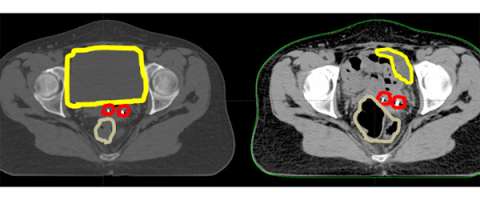

Here is an axial CT scan slice of an actual patient with her bladder full on the left and her bladder empty on the right. You can see that with the bladder (yellow) empty that additional bowel falls within the pelvis and that the marker seeds (red) are in a different place (also in part due to increased air in the rectum (brown). This example demonstrates the importance of daily image guidance and making sure that your bladder is consistently full during the course of your treatment.